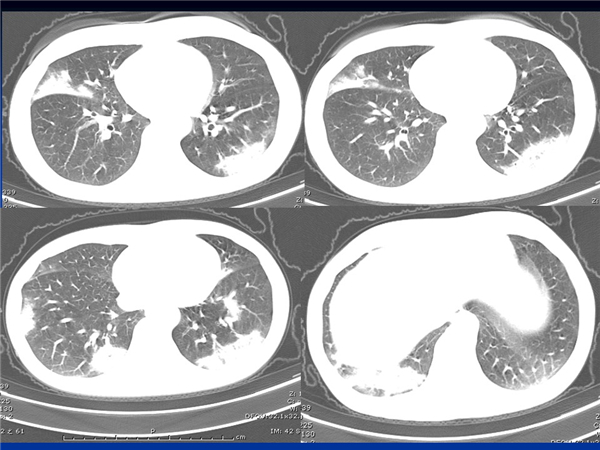

【病例分享】新型冠狀病毒感染肺部CT影像4例(常德市第一人民醫(yī)院)